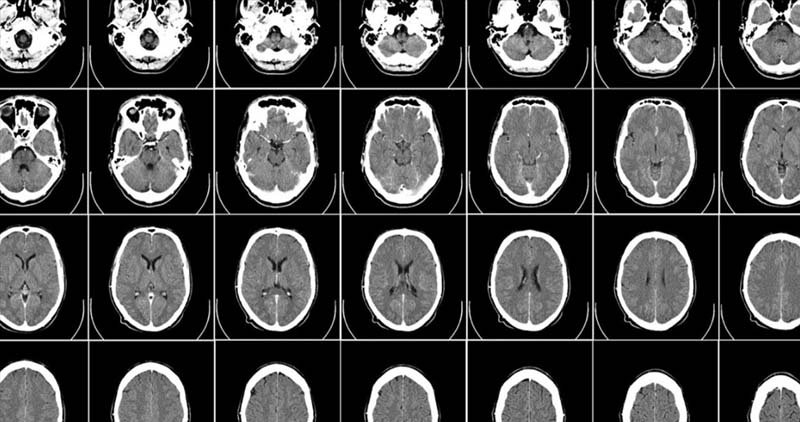

킹스칼리지런던의 연구원 겸 런던 AI 센터(London AI Center)의 CTO인 호르헤 카르도소(Jorge Cardoso)는 의료 연구원에게 무료로 제공되는 10만 개의 합성 뇌 이미지를 만들고 있다. 이는 치매, 노화 또는 모든 종류의 뇌 질환에 대한 이해를 가속화할 수 있는 보물창고이다.

카르도소는 교사, CTO, 기업가, MONAI 오픈소스 컨소시엄의 창립 멤버이자 의료 영상용 AI 연구원이다. 의료 영상용 AI 연구원의 역할에서 카르도소와 그의 팀은 AI를 사용해 인간 두뇌의 사실적인 고해상도 3D 이미지를 만드는 방법을 발견했다.

새로운 AI 접근 방식의 다행스러운 부분은 주문에 따라 이미지를 만들 수 있다는 것이다. 여성의 두뇌, 남성의 두뇌, 늙은 두뇌, 젊은 두뇌, 질병이 있거나 없는 두뇌 등 다양하며, 필요한 것을 연결하면 생성된다.

시뮬레이션 이미지이긴 하지만 이는 매우 유용하다. 주요 생물학적 특성을 보존하고 있어 실제 두뇌처럼 보이고 행동하기 때문이다.